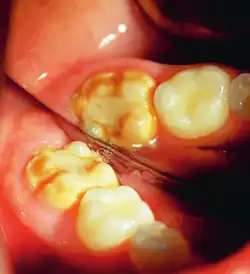

It occurs as a result of severe hypomineralization of the enamel as the enamel appears intact in the initial stages but gradually chips and fractures after the tooth erupts due to the weakened mineral content hence, leading to the formation of rough surfaces and cavities which makes the tooth highly vulnerable to undergo wear, decay and sensitivity.[26] Notably, the post-eruptive breakdown is linked to severe forms of hypomineralization like molar incisor hypomineralization (MIH).[27]

Enamel hypocalcification is characterized by the presence of white spots or streaks on the teeth due to reduced mineral content,[34] posing both cosmetic concerns and potential structural weaknesses. White spots can also be seen in patients. As the enamel undergoes demineralization, it becomes thinner, often leading to yellow or brown discoloration. The severity of this discoloration can range from mild yellowing to more pronounced brown staining, reflecting the extent of enamel loss.[7] This compromised enamel layer can also heighten tooth sensitivity to temperature changes and sugary foods, as external stimuli more easily reach the pulp, causing discomfort. Additionally, individuals with enamel hypocalcification experience a higher incidence of dental caries, as the weakened enamel provides less resistance to acid produced by oral bacteria.[19]

Enamel hypocalcification is characterized by visible defects in the enamel, often manifesting as white spot lesions or brown discolorations.[35] In cases such as dental fluorosis, this may include mottled patterns on the enamel surface which vary in appearance and extent based on the severity of the condition.[36] In advanced cases, the mottled appearance of the enamel can expose the underlying dentin, creating an uneven and sometimes porous surface. Though the matrix of the enamel initially forms to a typical thickness, the mineralization or calcification process is incomplete or deficient, leading to softer and structurally compromised enamel.[35]

This compromised enamel is more susceptible to staining due to its rougher surface texture and increased permeability, which allows pigments and external elements to penetrate more easily. The weakened enamel may begin to wear away, especially on the occlusal surfaces of the molars, where mechanical forces are most intense. In some individuals affected by severe enamel hypocalcification, the structural deficiencies also contribute to anterior open bite where the upper and lower front teeth do not meet when biting down. This malocclusion can further complicate both functional and aesthetic aspects of the dentition.[37]